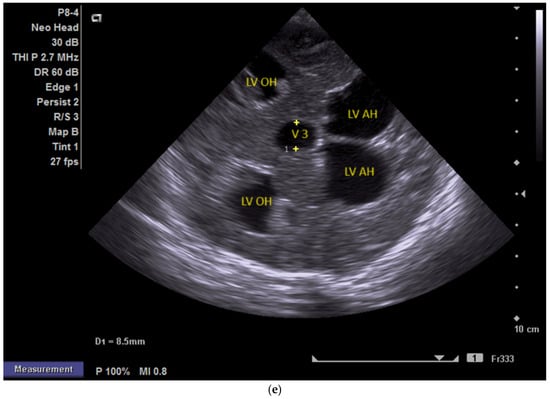

(a,b) MRI—T2 sequence. Sagittal view. Antenatal. Yellow arrows indicate the place of the suspected tumor (personal image collection). (c) Cranial ultrasound. Sagittal view. Up—enlarged left ventricle. D1—thamalo-occipital distance. Down—enlarged right ventricle. D1—thalamo-occipital distance (personal image collection). (d) Cranial ultrasound. Sagittal view. Enlarged third ventricle. Fourth ventricle is normal. D1, D2—measurements of the third ventricle (personal image collection). (e) Cranial ultrasound. Transtemporal view. Enlarged third ventricle. Sylvian aqueduct is not visible. D1—measurement of third ventricle. LV AH—lateral ventricle anterior horn. LV OH—lateral ventricle occipital horn. V 3—third ventricle (personal image collection).

After stabilization, the cranial ultrasound exam revealed enlargement of the lateral ventricles and third ventricle, with a normal fourth ventricle. There was no visualization of the Sylvian aqueduct, which raised the suspicion of aqueduct atresia or stenosis (Figure 5c–e). There was no improvement seen in the cranial ultrasound examinations that followed.